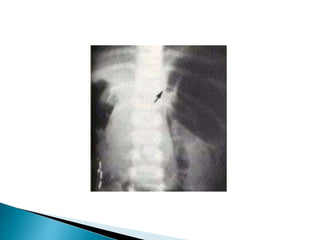

Dilated, air-filled duodenal bulb and paucity of

gas distally

"Double bubble sign" = air-fluid levels in

stomach & duodenum

o Isolated collection of gas-containing bowel

loops distal to obstructed duodenum = gas-

filled volvulus = closed-loop obstruction

From non resorption of intestinal gas

secondary to obstruction of mesenteric veins